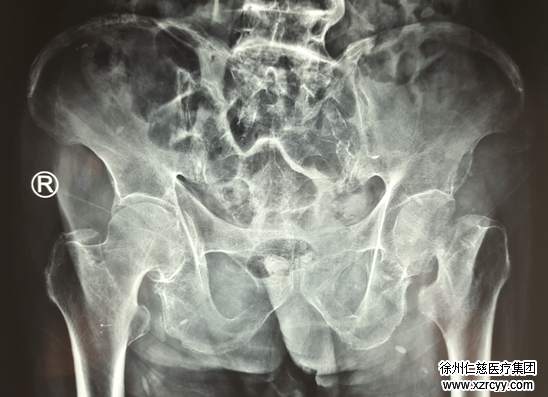

术前片